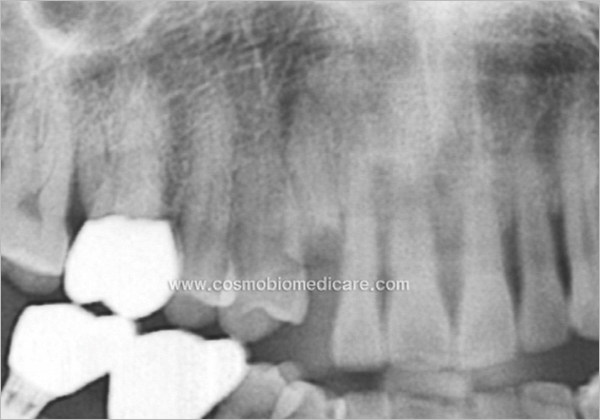

Clinical Cases

Histologic slide (3 Months Post OP.)

• 3 Months Post OP.[ H&E x 100 ]

• 3 Months Post OP.[ M&T x 100 ]